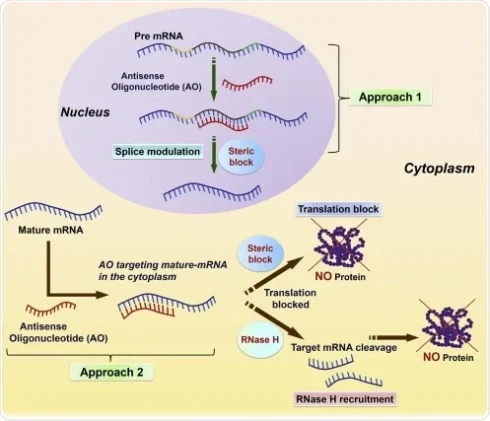

فناوری آنتی سنس در کشف دارو

مقدمهای بر فناوری آنتی سنس در کشف دارو مفهوم فناوریهای الیگونوکلئوتیدی آنتیسنس مبتنی بر مسدود[بیشتر بخوانید]